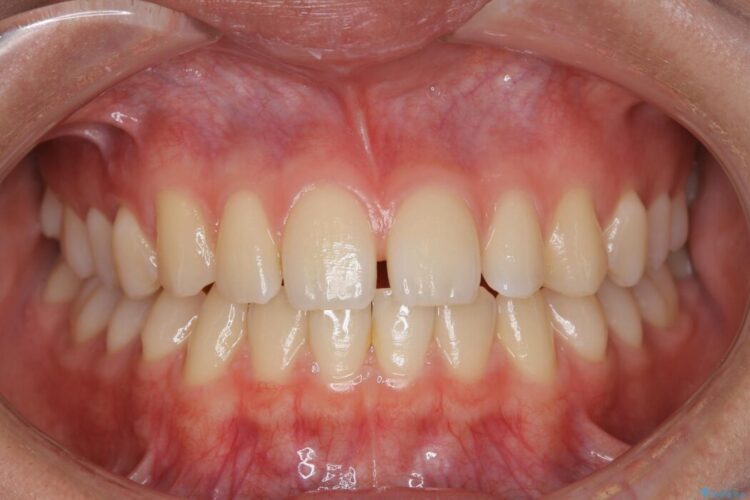

すきっ歯を改善したいとご来院された患者様です。

マウスピース14枚・期間4ヶ月で主訴であるすきっ歯を改善し、治療を終えることが出来ました。